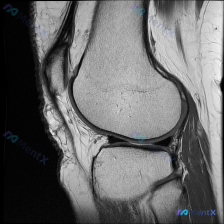

距骨内见边界清晰类圆形高信号伴低信号环,大家怎么分析?

刚看到一份足踝部矢状位MRI的影像资料,病灶特征很典型,整理一下病例和我的分析思路,和大家交流。

这是T2加权或质子密度加权脂肪抑制序列的MRI,主要发现如下:

- 核心病灶:距骨体部内部可见一个圆形/类圆形、边界清晰的高信号影,周围伴有低信号环,是典型的骨内病灶

- 其他结构评估:胫骨远端、距骨、跟骨、舟骨等骨骼轮廓完整;踝关节、距下关节间隙无明显弥漫狭窄;跟腱、屈趾长肌腱等主要肌腱连续性良好,无明确撕裂;皮下软组织、足底筋膜未见明显异常肿胀或水肿;没有发现骨质破坏、软组织肿块或骨膜反应

看到「中心高信号+周围低信号环」这种典型影像表现,第一反应这是良性的骨内局灶性病变,低信号环基本代表周围的反应性骨硬化或者纤维包膜,暂时不考虑恶性病变,但需要按顺序做鉴别。